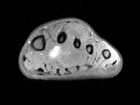

21 year old male with swelling and pain in left foot for six months

Zoom image: Radiological image Radiological image.